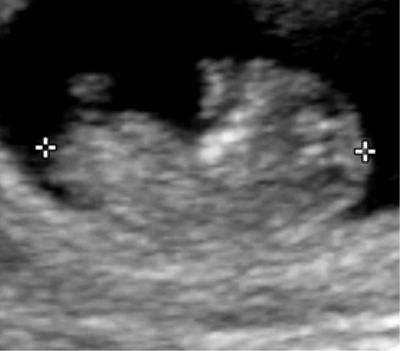

Embryon de 10 semaines d'aménorrhée.